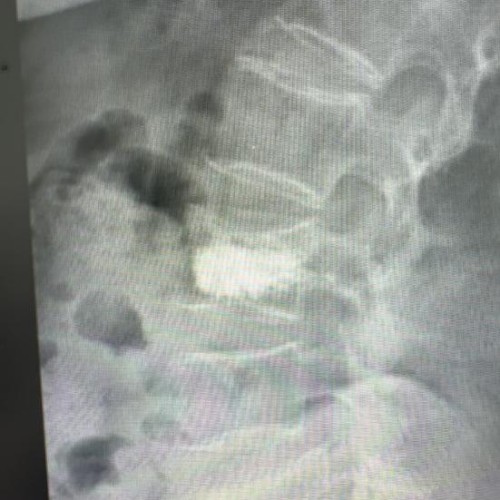

面对家属“希望老人尽快摆脱疼痛、重新站起来”的迫切愿望,骨科主任高胜一迅速组织多学科会诊。团队结合患者影像学检查结果、全身状况综合评估,在充分与家属沟通手术风险与预期获益后,最终确定采用经皮椎体后凸成形术(PKP)方案。该手术具有创伤小、恢复快的优势,通过背部小切口,在影像设备精准定位下插入球囊扩张器恢复椎体高度,再注入骨水泥稳定椎体结构,可有效缓解疼痛并避免长期卧床并发症。

经详细术前评估与充分准备,手术当日,高胜一与副主任医师杨兆平紧密配合,顺利穿刺并注入骨水泥,整个操作过程精细流畅,耗时约30分钟。王奶奶麻醉苏醒后,便明显感觉到折磨多日的腰背剧痛大幅减轻。次日,在医护人员指导下,老人顺利下床行走,有效避免了长期卧床可能引发的各类并发症。看着老人重新露出的笑容,家属悬着的心终于落了地。目前王奶奶已顺利康复出院,回归正常的家庭生活。